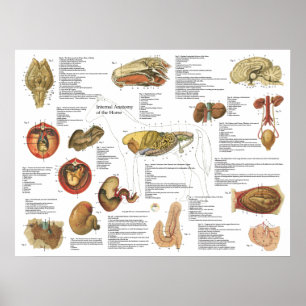

Poster Opiniões de um feto na mulher,Ob-Gyn Medical

Preço151,00 €